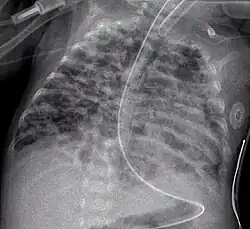

A chest X-ray showing a very prominent wedge-shape area of airspace consolidation in the right lung characteristic of acute bacterial lobar pneumonia.